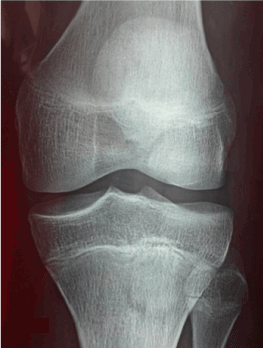

We report the case of the 5 years old boy with no significant pathological history who consulted our emergencies for a painful stiffness of the left knee following a 15 days after trauma. The child was apyretic, the knee was swollen with the presence of a patellar shock. The palpation of internal articular interlining is painful. There was a knee reducible flessum of 30 °. The standard radiography showed a discreet enlargement of the internal articular interlining (Figure 1). MRI showed a bucket handle injury of the internal meniscus (Figure 2). A partial meniscectomy under arthroscopy was performed. In peroperative we discovered an incomplete discoid medial meniscus (type II Watanabe), with presence of an extended lesion of  the medial meniscus. The patient had a resection of the dislocated part with regularization of the axial margin of the internal meniscus, thus producing an arched shape similar to the normal shape. The operative sequences were simple. The patient is asymptomatic until now at 5 years of follow-up. The functional result was excellent with complete knee mobility and normal sports activity.

Figure 1. Radiography of the knee of the face: enlargement of the articular space internally